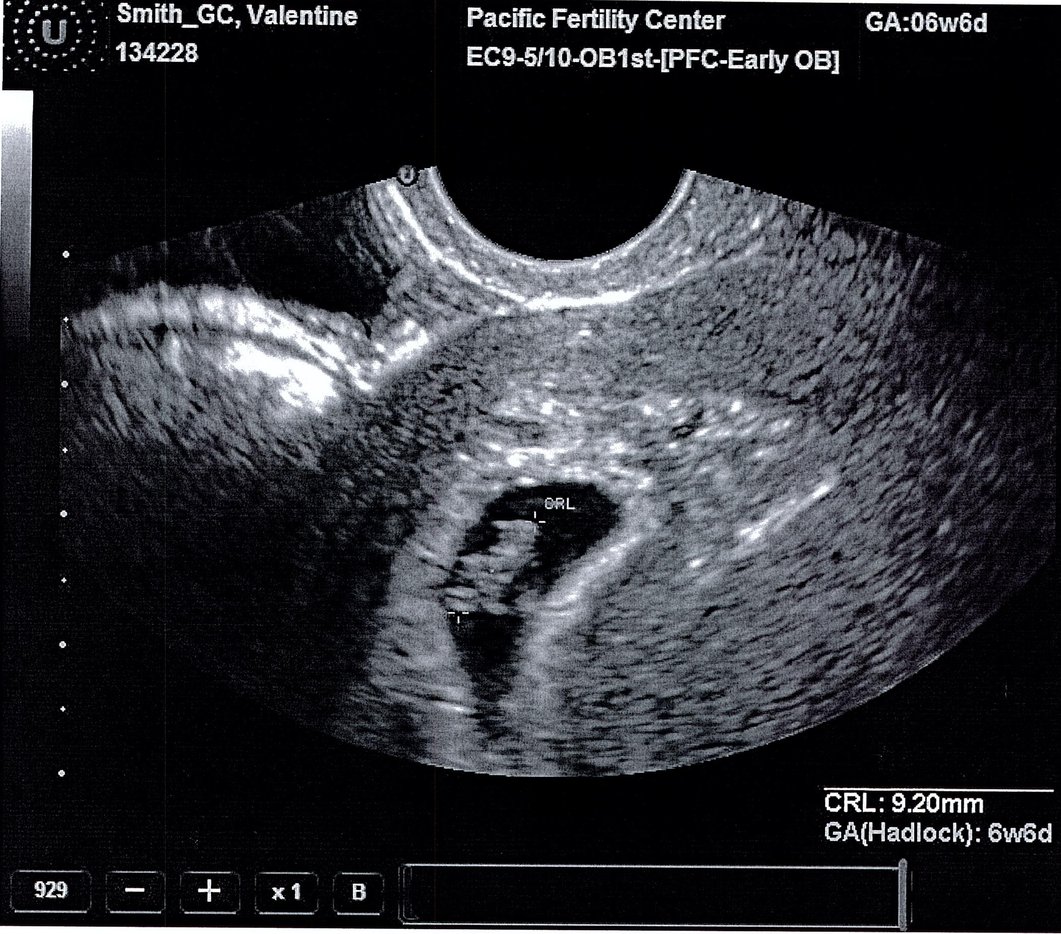

They measured that I was at 6 weeks & 6 days - perfectly normal. We were able to see and hear the tiny heart beat! We even saw the itty bitty head & body forming. I don't think I had ultrasounds this early with my own, so it was amazing to see it in such small form! The clinic gave the father a USB of the images and I asked them to print me a couple as well. :) Here are my souvenirs:

In the above shot, the curser shows the lenth of the body. The baby's head is

at the top curser (below the "CRL").